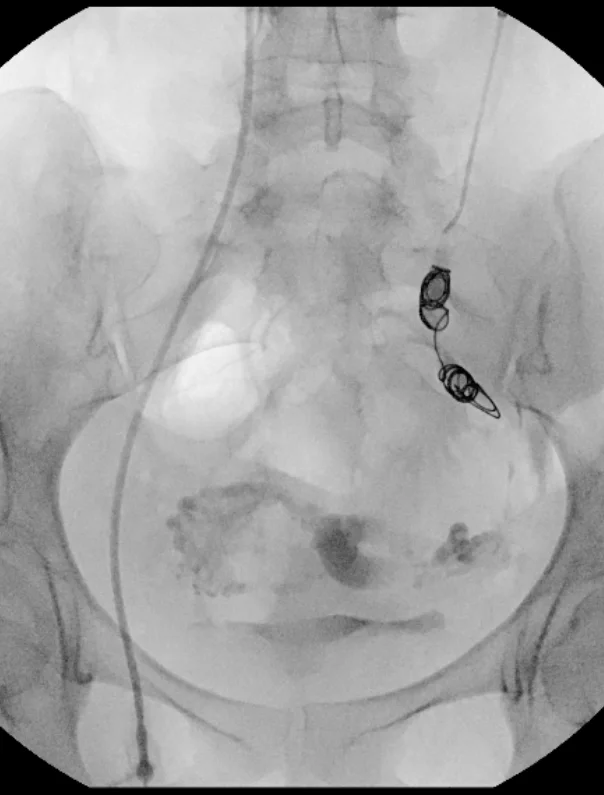

The most common treatment option is ovarian vein embolization. This outpatient procedure performed in our office involves blocking the abnormal blood flow in the pelvis by using x-ray guidance to navigate catheters through the veins and deposit sclerosants and metal coils. The veins will scar down, deflating the dilated, abnormal veins, and relieving symptoms. Patients go home in a few hours and recover completely in 1-2 days. Most patients have complete relief of symptoms within 4-6 weeks.

before Treatment of PCS

after PCS treatment

After Treatment of PCS